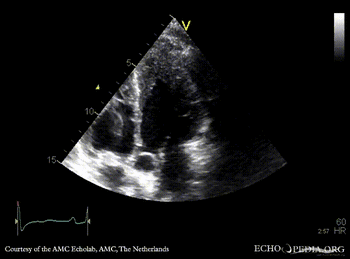

Case 42